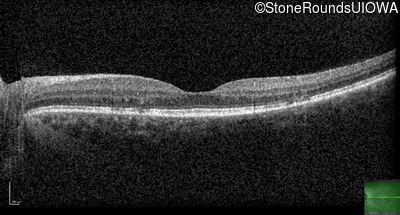

Optical Coherence Tomography - Right - 20/20 -1

Exemplar / OCT Stack

OCT Stack